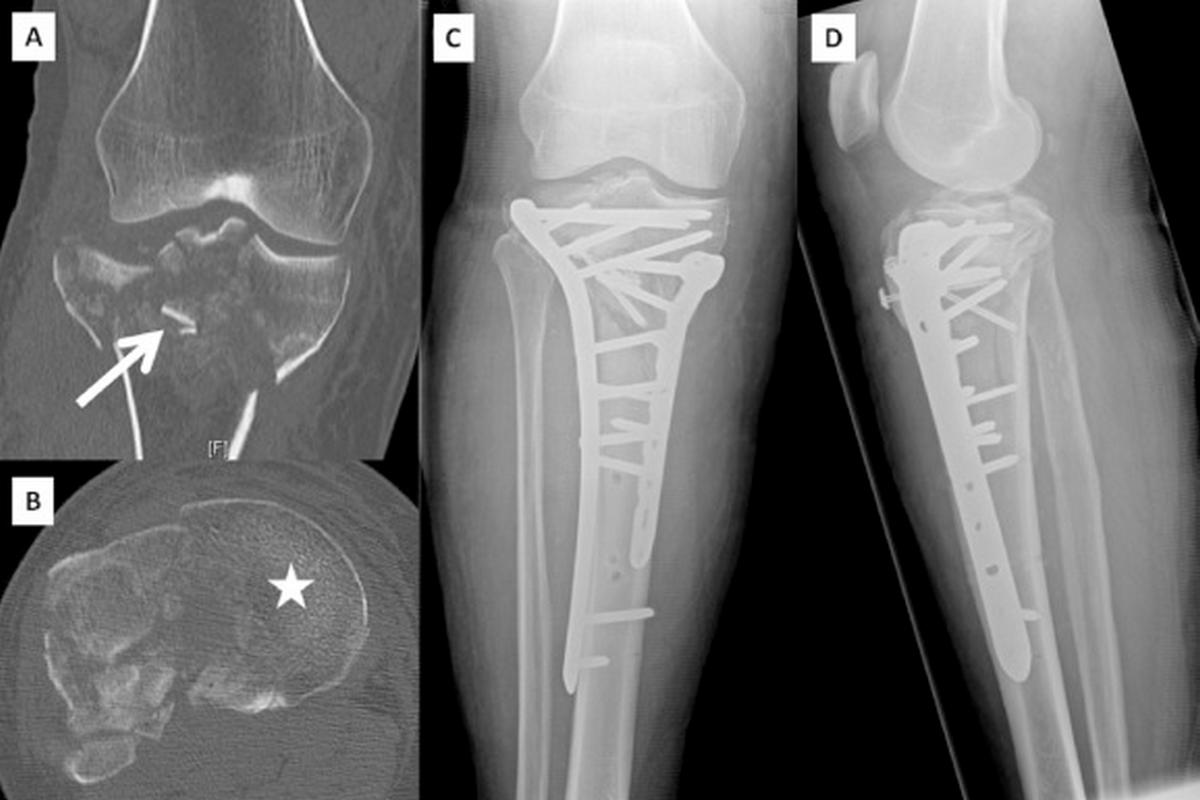

Οι ασθενείς παρουσιάζουν έντονο πόνο, οίδημα, αδυναμία στήριξης του σκέλους και συχνά εμφανή παραμόρφωση. Η διάγνωση γίνεται με ακτινογραφίες, ενώ η αξονική τομογραφία είναι απαραίτητη για την ακριβή εκτίμηση της γραμμής και της πολυπλοκότητας του κατάγματος.

Η θεραπεία είναι κατά κανόνα χειρουργική και περιλαμβάνει οστεοσύνθεση με πλάκες και βίδες ή ενδομυελικούς ήλους, με στόχο την ανατομική ανάταξη και τη σταθερότητα. Συντηρητική αγωγή εφαρμόζεται σπάνια και μόνο σε ασθενείς που δεν μπορούν να υποβληθούν σε χειρουργείο.

Πιθανές επιπλοκές είναι η μη πώρωση, η δυσκαμψία του γόνατος και η ανάπτυξη μετατραυματικής αρθρίτιδας.

Ιδιαίτερη σημασία έχουν οι συνοδές βλάβες σε μηνίσκους και συνδέσμους, οι οποίες επηρεάζουν την πρόγνωση. Εκτός από τις ακτινογραφίες, σχεδόν πάντα απαιτείται αξονική τομογραφία για λεπτομερή χαρτογράφηση του κατάγματος.

Μη παρεκτοπισμένα κατάγματα μπορούν να αντιμετωπιστούν συντηρητικά με ακινητοποίηση, αποφόρτιση και σταδιακή κινητοποίηση. Παρεκτοπισμένα ή ενδοαρθρικά κατάγματα απαιτούν χειρουργική ανάταξη και σταθεροποίηση με πλάκες ή βίδες. Η φυσικοθεραπεία είναι απαραίτητη για την πρόληψη δυσκαμψίας και δευτερογενούς αρθρίτιδας.